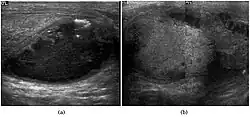

Seminoma is the most common tumor type in cryptorchid testes. The risk of developing a seminoma is increased in patients with cryptorchidism, even after orchiopexy. There is an increased incidence of malignancy developing in the contralateral testis too, hence sonography is sometimes used to screen for an occult tumor in the remaining testis. On US images, seminomas are generally uniformly hypoechoic, larger tumors may be more heterogeneous [Fig. 3]. Seminomas are usually confined by the tunica albuginea and rarely extend to peritesticular structures. Lymphatic spread to retroperitoneal lymph nodes and hematogenous metastases to lung, brain, or both are evident in about 25% of patients at the time of presentation.